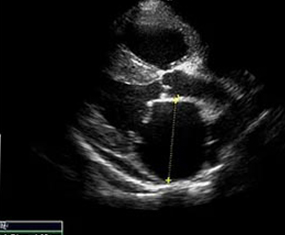

We elected to offer not only abdominal, cardiac and small parts ultrasound but also provide interventional procedures necessary to fulfill the diagnostic pathway. By doing so, we are capable of scanning a patient, working with attending veterinarians to assess patients for biopsy or aspiration and then collecting any samples that may be required to accurately diagnose and address the underlying concern.

At RVUS we have chosen industry leading equipment from vendors with reputable and proven track records in the industry. From the front lines to your final report it is imperative that the equipment and the user provide images that equip the specialists with the highest level of quality and reproducibility to confidently provide an accurate interpretation of the sonogram.

This, in turn, provides you with additional tools to arrive at a diagnosis and prognosis and to enhance the care model for your patient and confidence with your client. Our team of professionals with decades of ultrasound experience encourage the use of ultrasound as a leading route to non-invasively assess organs and pathology in question. To cover that spectrum, a variety of transducers are essential, all with different characteristics.

Whether your patient is 100 lbs or 10 lbs, take comfort in knowing your sonographer is capable of generating images that are sensitive and specific to the clinical concerns.